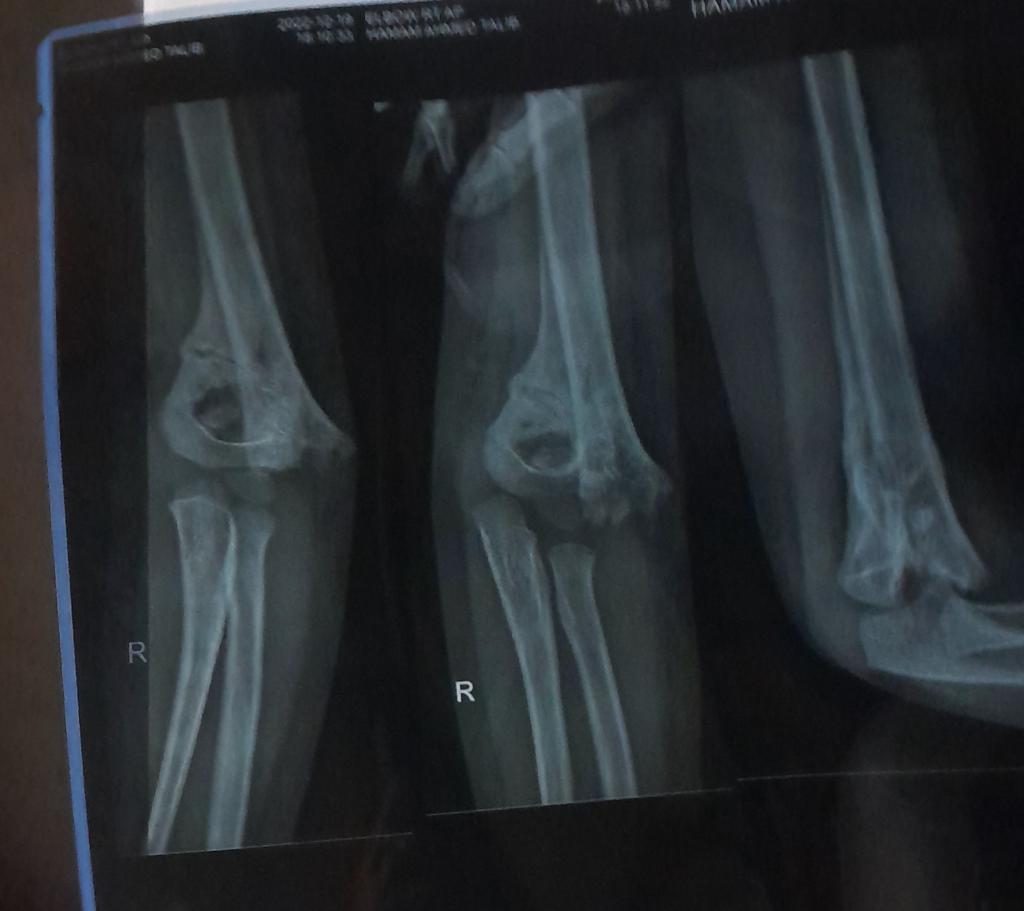

انا اعرف دكاترة عظام. تحبين ترسلين صور اشعه ع الخاص هنا ويشوفونها ويشخصون تفضلي

ايه ياريت بحاول ارسلهم لك بالخاص

هذيك صورة الاشعه وهذه صورة يده